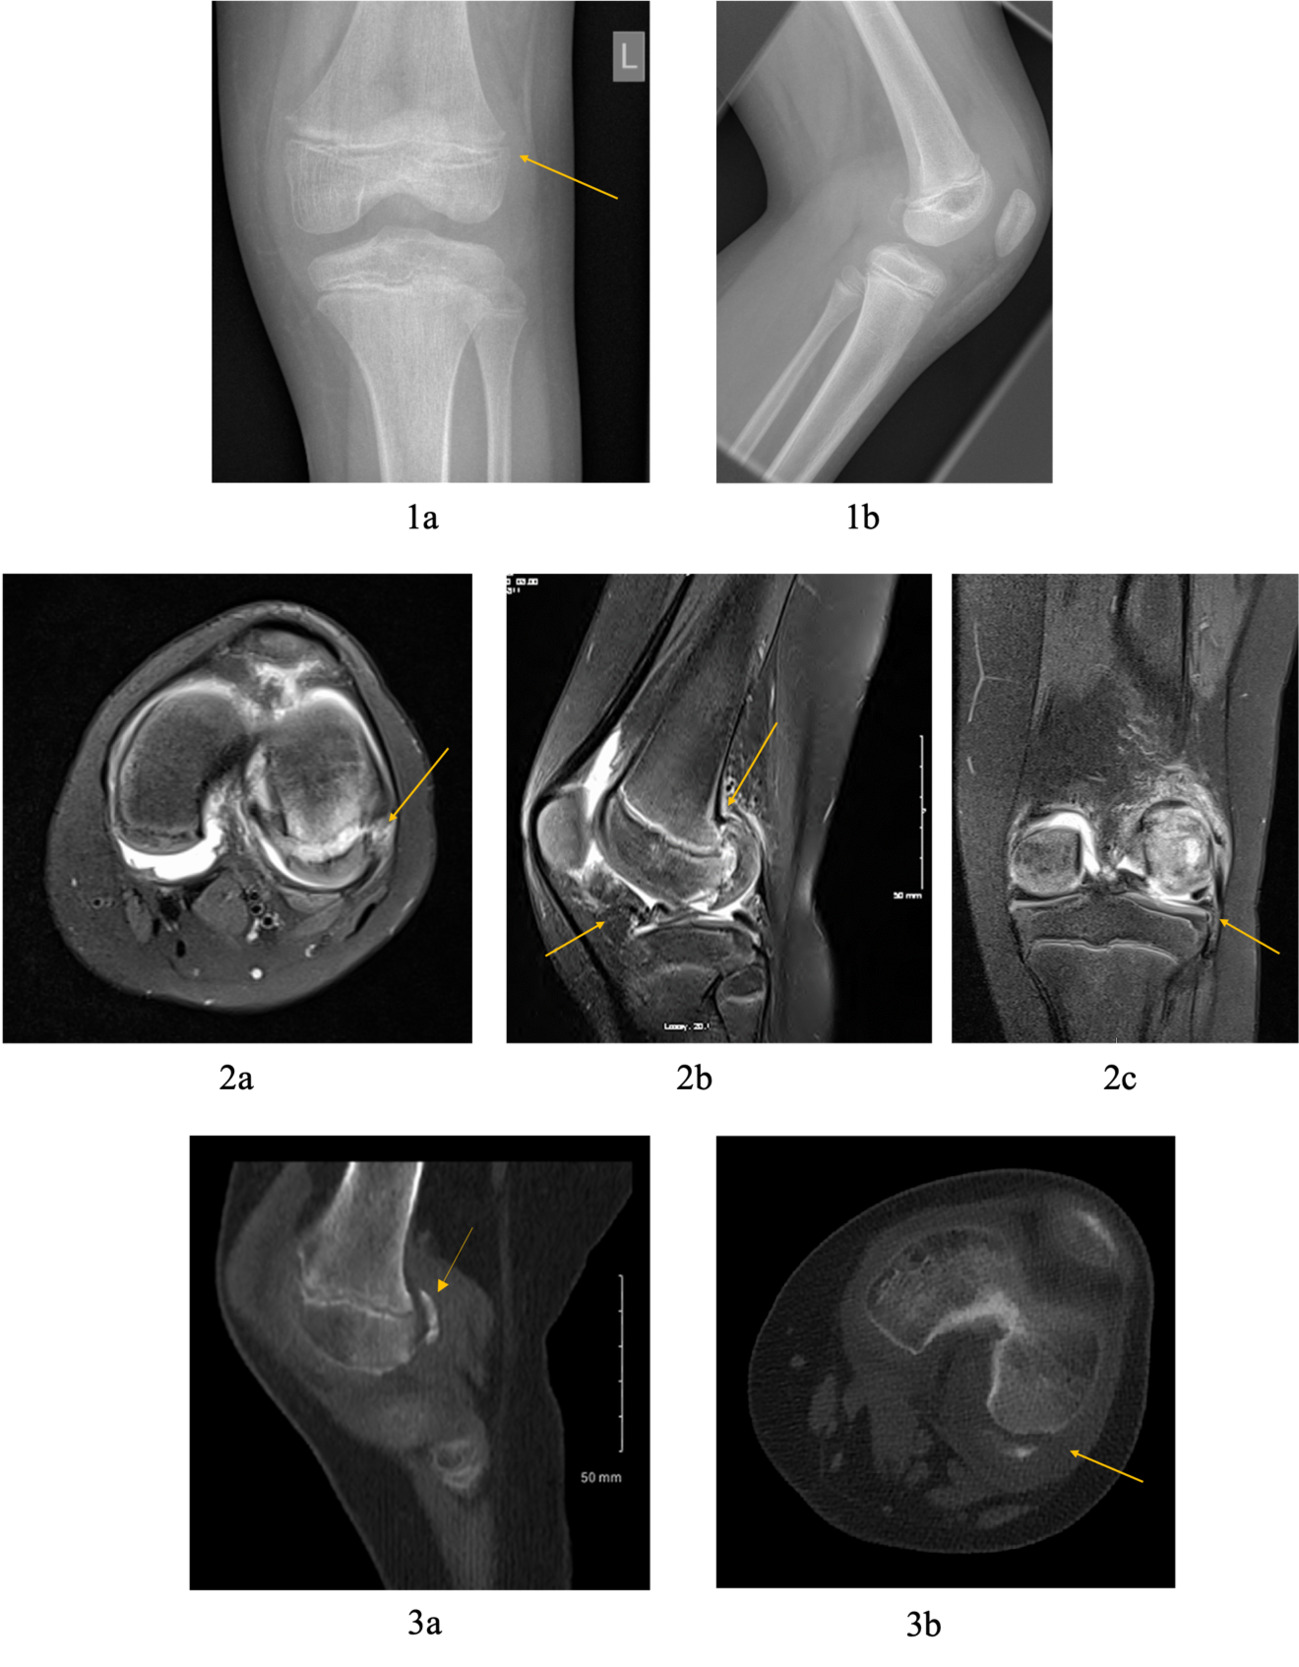

Initial lateral knee plain radiograph confirmed a large joint effusion with what looks like an associated rim of calcification posteriorly, while the anteroposterior (AP) radiograph was essentially normal with only subtle calcification around the lateral femoral condyle. (Fig 2)

Further imaging included a magnetic resonance imaging scan (MRI), followed by a computed tomography (CT) scan to aid pre-operative planning. MRI confirmed a Busch-Hoffa fracture of the lateral femoral condyle with an associated lateral meniscal bucket handle tear. CT scan showed the extent and the orientation of the condylar fragment. (Fig 2)